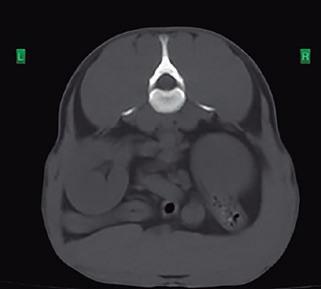

Issuu converts static files into: digital portfolios, online yearbooks, online catalogs, digital photo albums and more. Sign up and create your flipbook.